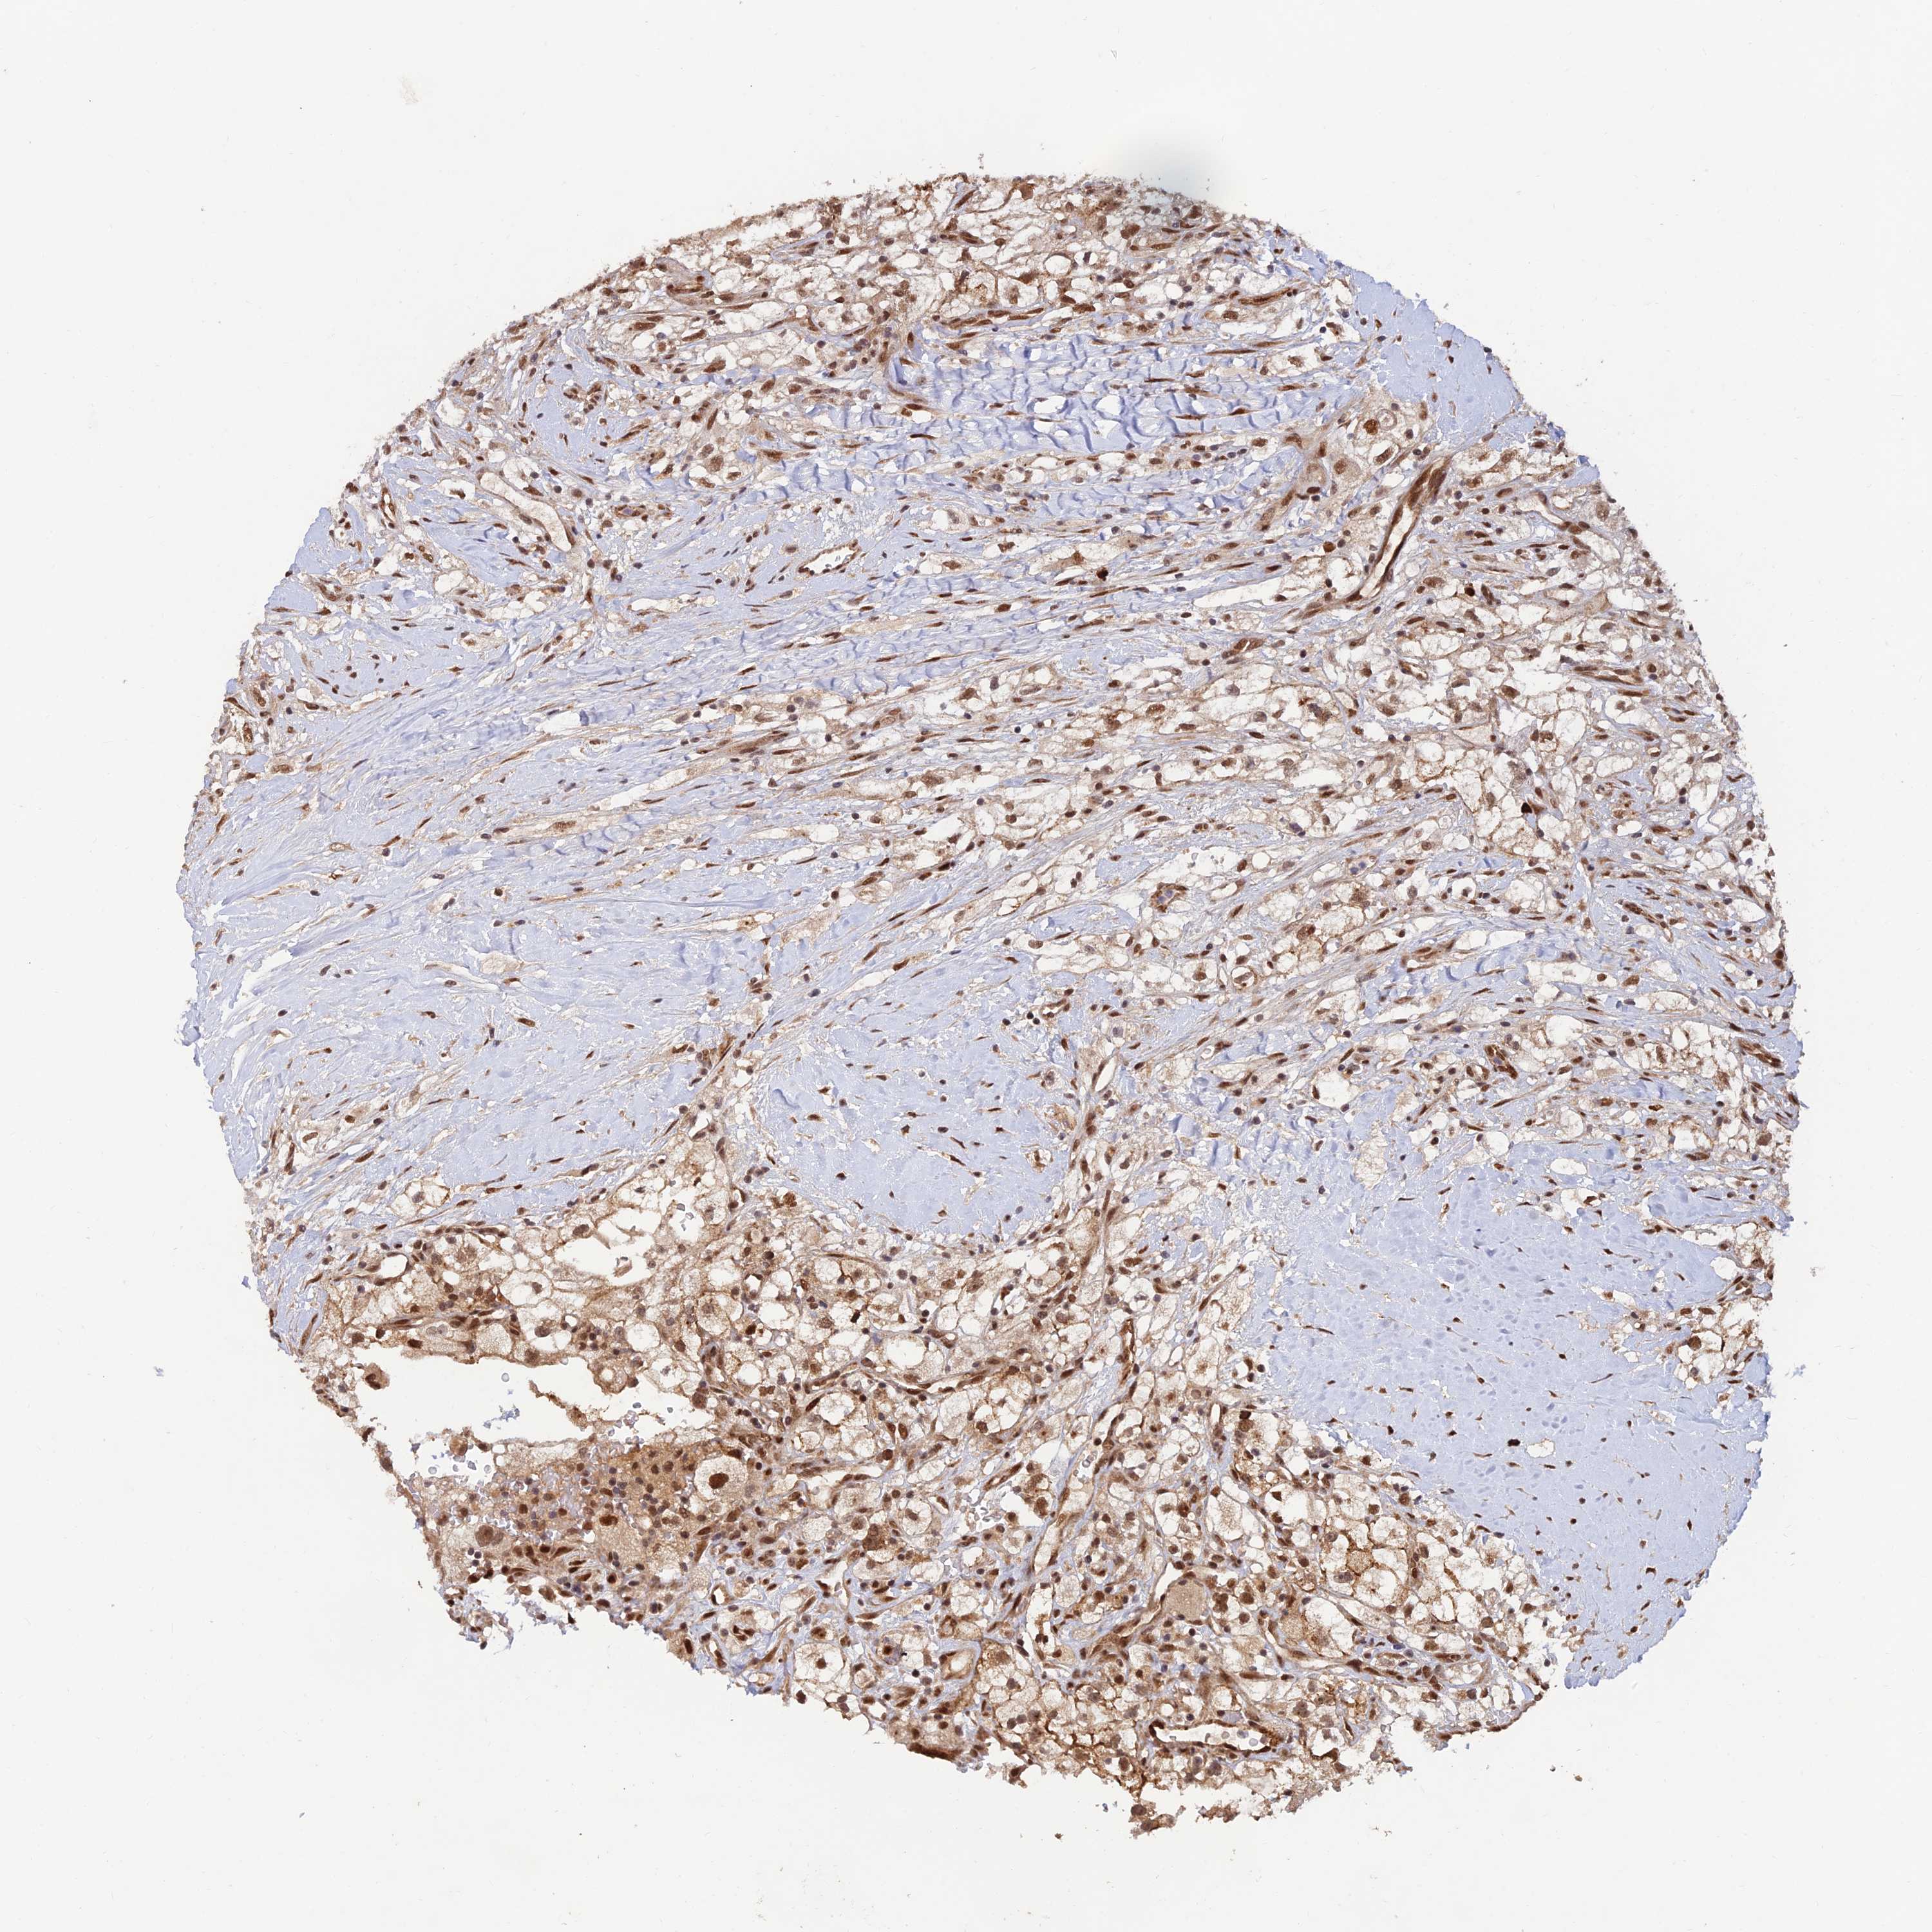

KICH TCGA KIRC TCGA KIRC VALIDATION KIRP TCGA PROTEIN RCC CPTAC PROTEIN EXPRESSION

KIDNEY RENAL CLEAR CELL CARCINOMA (VALIDATION) - Interactive survival scatter ploti

The Survival Scatter plot shows the clinical status (i.e. dead or alive) for all individuals in the patient cohort, based on the same data that underlies the corresponding Kaplan-Meier plots. Patients that are alive at last time for follow-up are shown in blue and patients who have died during the study are shown in red.

The x-axis shows the expression levels (FPKM) of the investigated gene in the tumor tissue at the time of diagnosis. The y-axis shows the follow-up time after diagnosis (years). Both axes are complimented with kernel density curves demonstrating the data density over the axes. The top density plot shows the expression levels (FPKM) distribution among dead (red) and alive patients (blue). The right density plot shows the data density of the survived years of dead patients with high and low expression levels respectively, stratified using the cutoff indicated by the vertical dashed line through the Survival Scatter plot. This cutoff is automatically defined based on the FPKM cutoff that minimizes the p-score. The cutoff can be changed by dragging the vertical line or by entering a cutoff value in the square labeled "Current cut-off".

Under the Survival Scatter plot the p-score landscape (black curve; left axis) is shown together with dead median separation (red curve; right axis). Dead median separation is the difference in median mRNA expression between patients who have died with high and low expression, respectively. It is calculated as follows: median FPKM expression of dead patients with high expression - median FPKM expression of dead patients with low expression. This is intended to aid the user in visually exploring custom cutoffs and the associated p-scores and dead median separation.

Individual patient data is displayed and can be filtered by clicking on one or more of the category buttons on the top of the page. Categories describing expression level and patient information include: high, low, alive, dead, female, male and tumor stages. The scale of the x-axis can be toggled between linear and log-scale by clicking on the "x log" button. Mouse-over function shows TCGA ID, patient information and mRNA expression (FPKM) for each patient.

& Survival analysisi

Kaplan-Meier plots summarize results from analysis of correlation between mRNA expression level and patient survival. Patients were divided based on level of expression into one of the two groups "low" (under cut off) or "high" (over cut off). X-axis shows time for survival (years) and y-axis shows the probability of survival, where 1.0 corresponds to 100 percent.

ZNF565 is not prognostic in Kidney Renal Clear Cell Carcinoma (validation)

: 2.91

Average pTPM 3.3

Number of samples 100